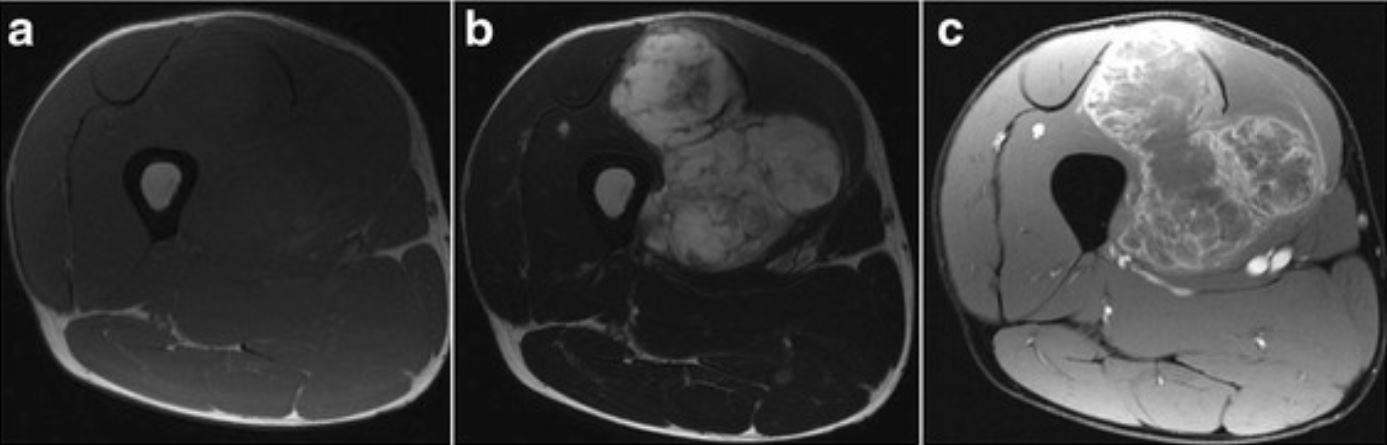

Em imaging

Em imaging 57 фотографий